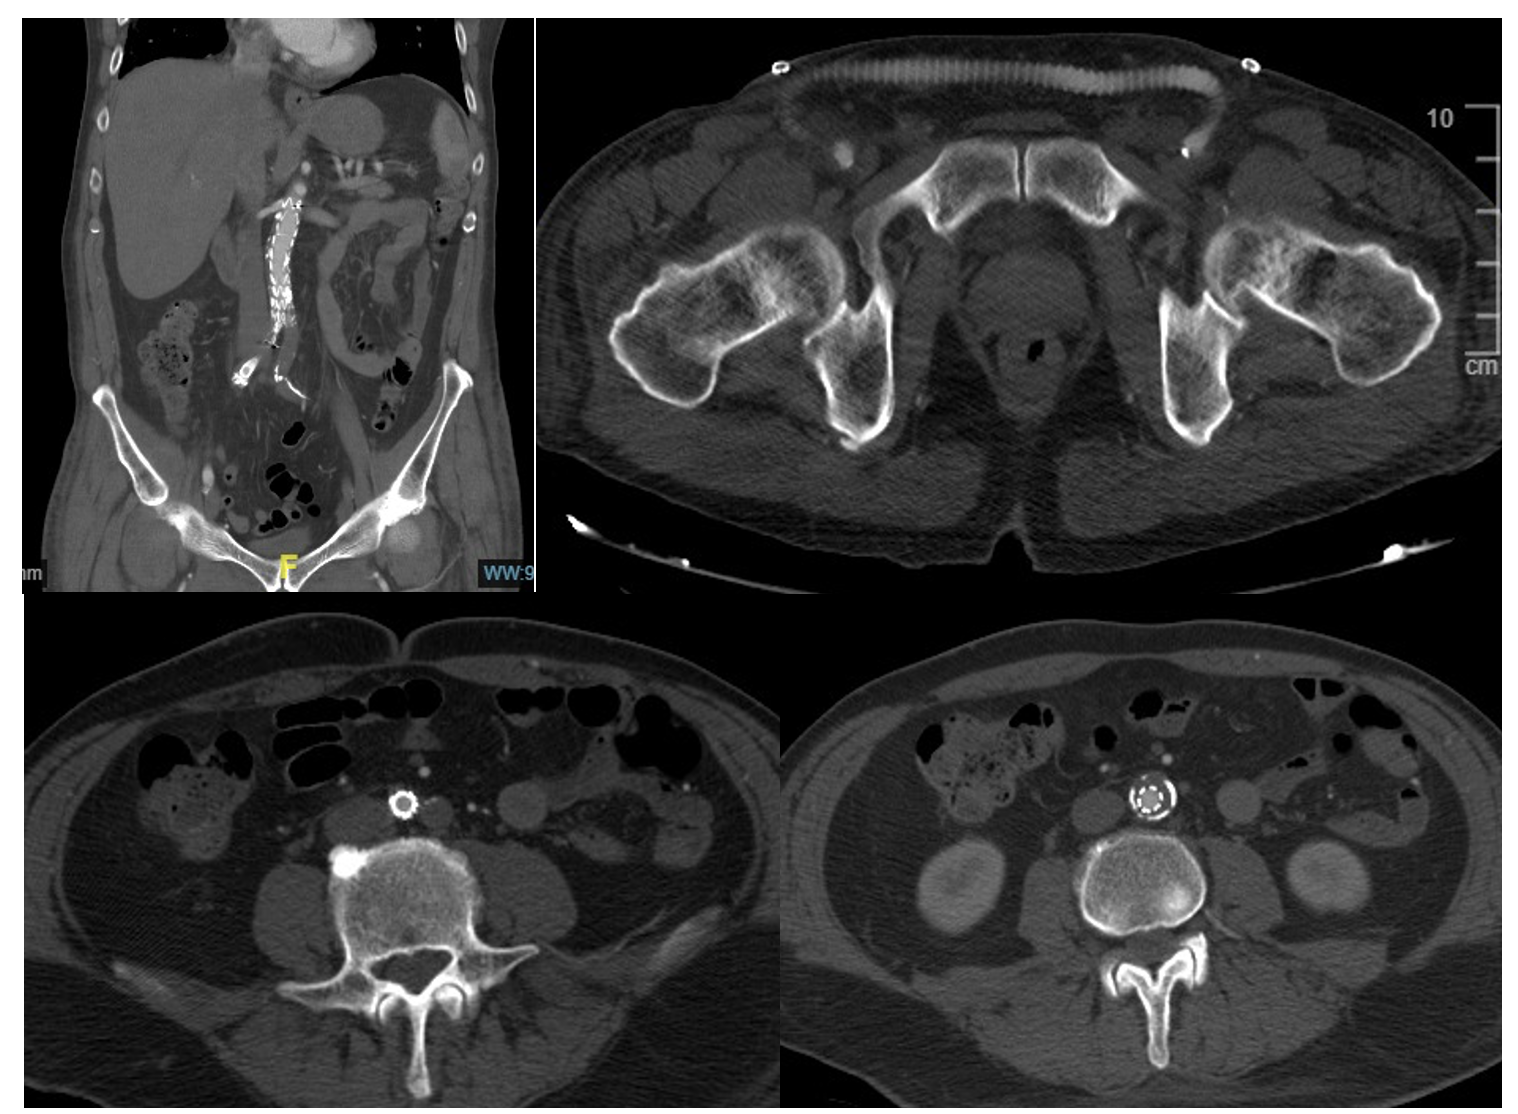

He presented to the ED 5 days later with pain, paralysis, and bilateral anesthesia of the lower limbs of 3 hours' duration, presenting with pulselessness at any level, with cutaneous lividity in the abdomen and both thighs on physical examination. The electrocardiogram showed new-onset AF, and an aorta computed tomography (CT) scan revealed complete acute occlusion of the infrarenal aorta and bilateral iliac arteries, along with chronic occlusion of the LEIA (Figure 1).

Given the possibility of isolating thrombotic debris from the infrarenal aorta and both iliac axes, a 16 x 10 aortic endograft (Medtronic) was implanted, extending to the right common iliac artery with a Viabahn VBX 8 x 79 stent graft (Gore), a right-to-left femorofemoral bypass using 8-mm ringed polytetrafluoroethylene catheter to restore vascularization to the left leg, and bilateral fasciotomies of the anterior and posterior compartments.